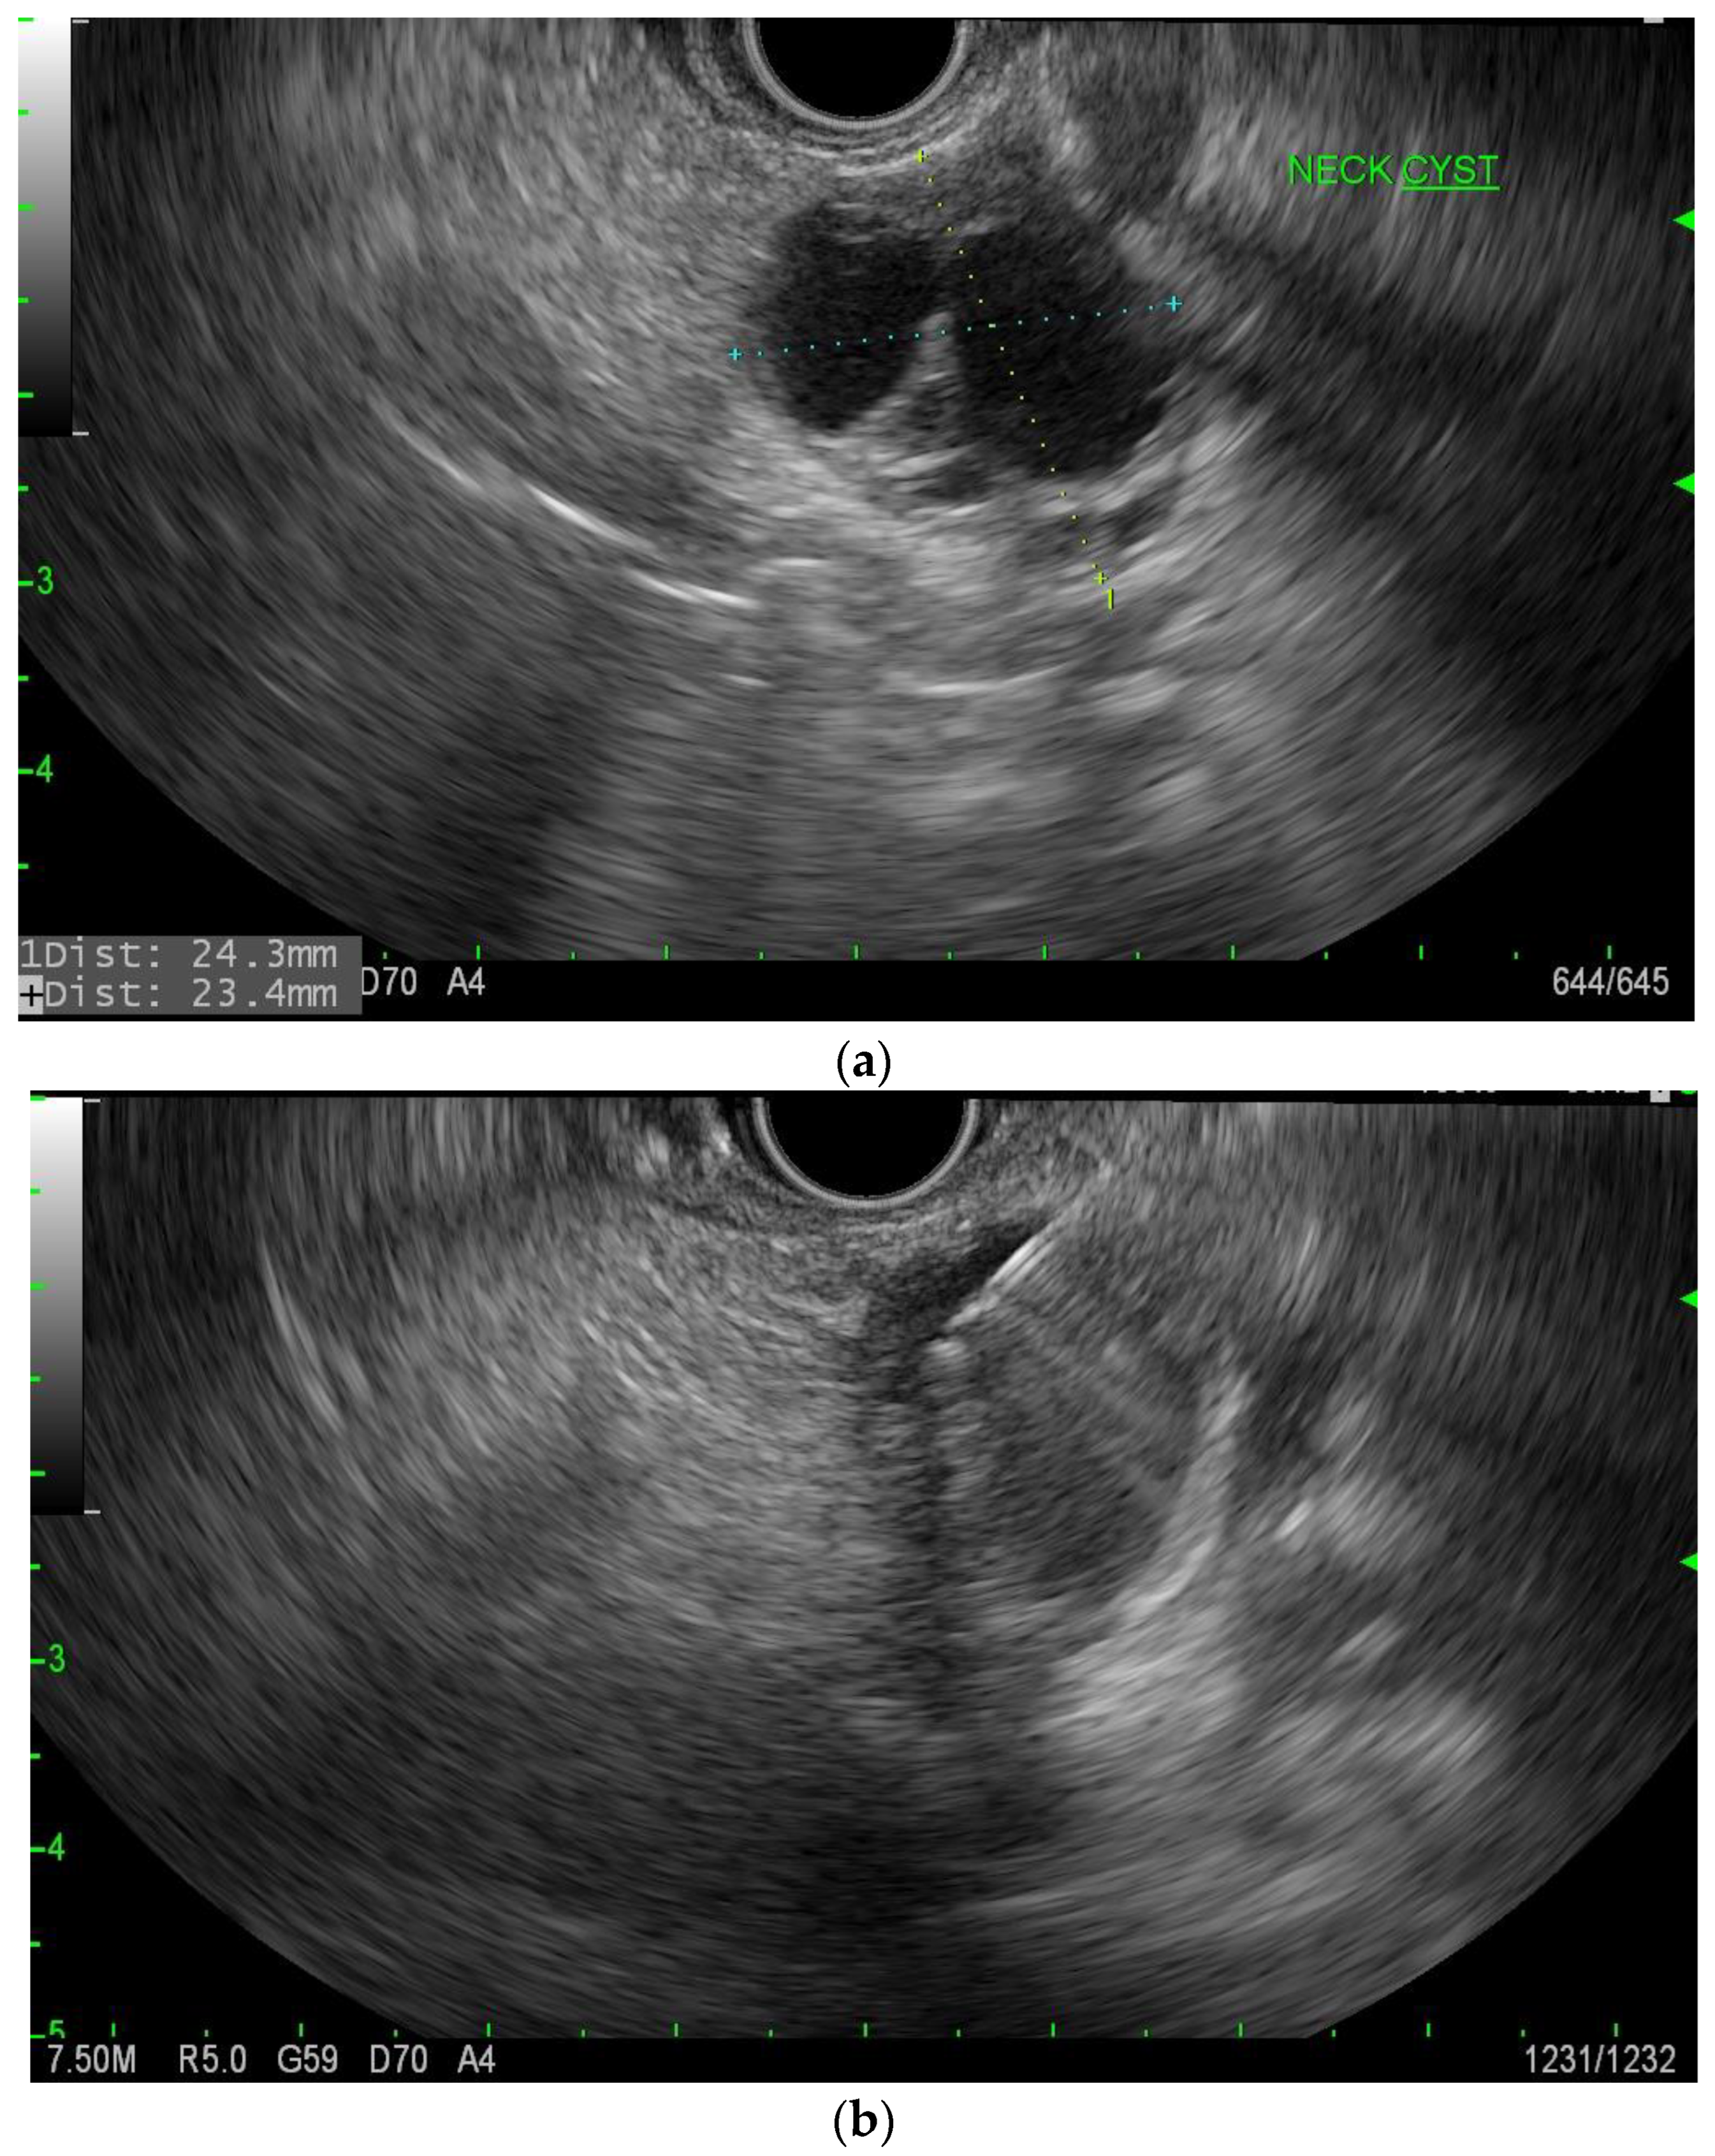

cNET’s age of presentation varies but usually is in the fifth to sixth decade of life [15]. Imaging usually demonstrates a solid and cystic mass, which is hypervascular (Figure 6). There is usually no connection with the main pancreatic duct, and the malignant potential is 10% [20]. However, pre-operative diagnosis given their small size, and therefore, EUS with FNA has been helpful in that immunostaining of neuroendocrine markers such as synaptophysin and chromogranin-A can differentiate between other types of PCN (Figure 7a,b) [21]. cNET has malignant potential but is very rare in general, and therefore the absolute malignancy risk is difficult to determine. In a systematic review of 64 patients with cystic neuroendocrine tumors, six (9.7%) patients were found to have carcinoma, though these were all resected tumors, so this is likely a higher estimation than the absolute malignancy risk [20].

Figure 7.

(a). EUS of cNET of the pancreas. (b). EUS-FNA of cNET of the pancreas.